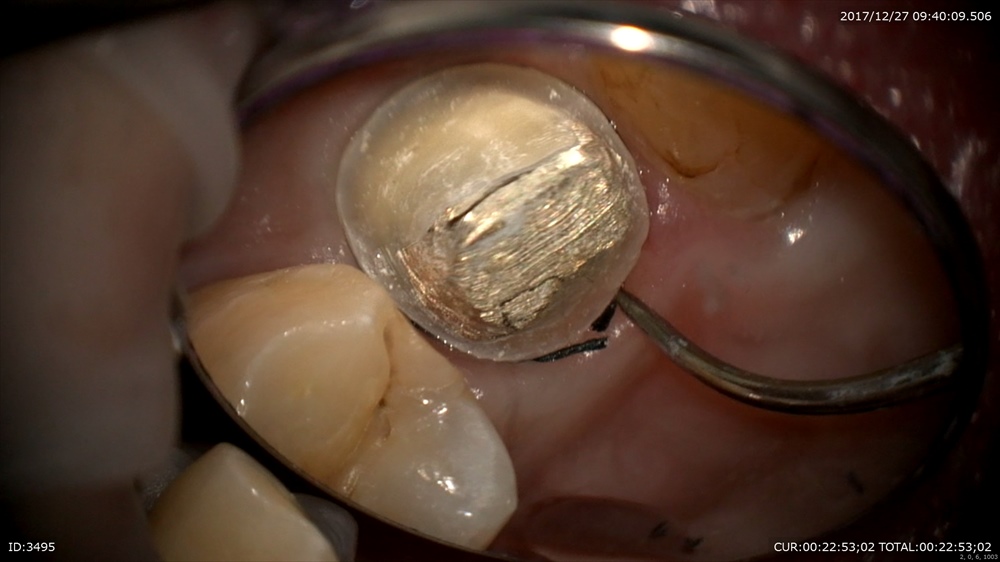

次の患者さまは精密根管治療

ラバーダムで準備

結構汚れています

綺麗にします。根管内の細菌がぐっと減りました。